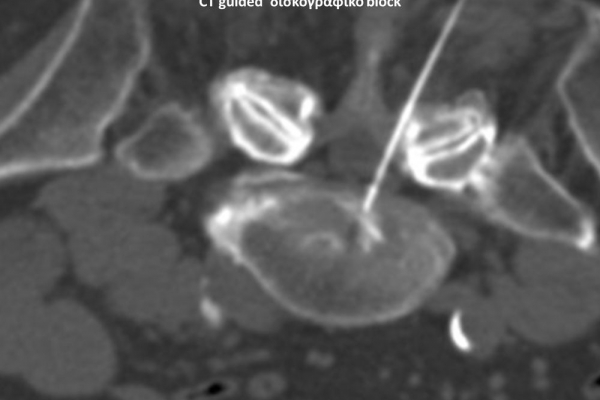

Με την βοήθεια της επεμβατικής ακτινολογίας είναι δυνατόν να πραγματοποιηθούν διαφορες ενέσιμες τεχνικές που αποσκοπούν στη μείωση του μυοσκελετικού πόνου, την ενίσχυση της αποτελεσματικότητας της φυσιοθεραπείας και την επιτάχυνση της διαδικασίας επούλωσης. Οι τεχνικές αυτές περιλαμβάνουν την κατευθυνόμενη έγχυση φαρμάκων ή πραγματοποίηση θεραπευτικών χειρισμών ακριβώς στη θέση τηςπαθολογία. Ετσι εξασφαλιζεται η μέγιστη αποτελεσματικότητα ( έως 95% κατά περίπτωση) και ασφάλεια σε σχέση με τυφλούς χειρισμούς χωρίς ακτινολογική καθοδήγηση.